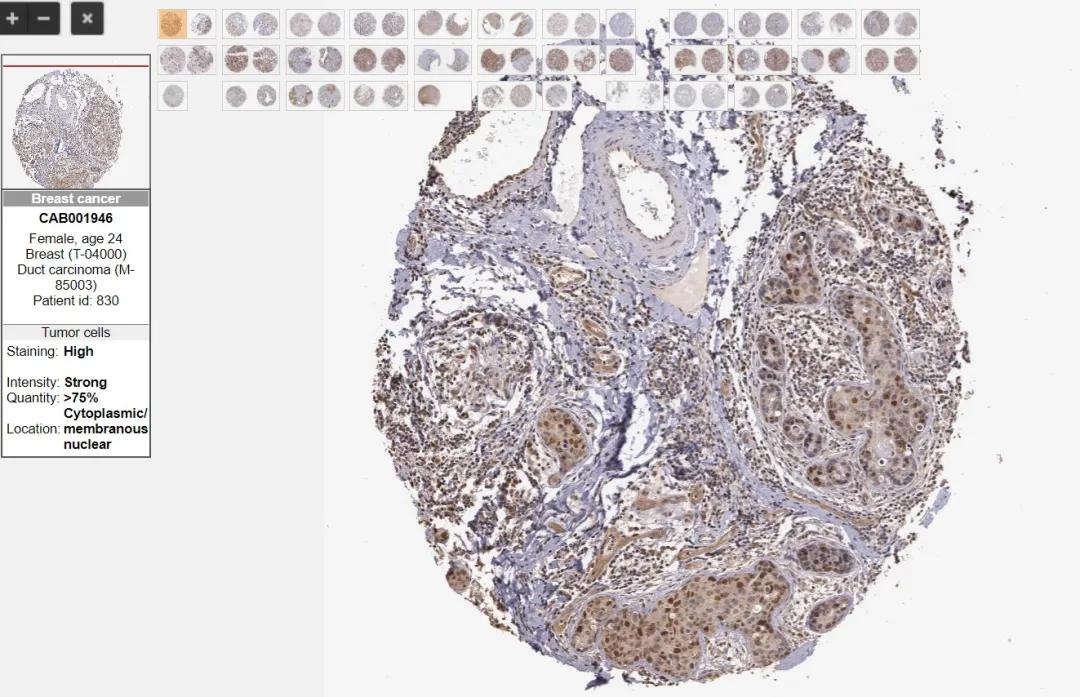

在正式实验前,可以先做些功课,可通过阅读文献或者公共数据网站,查看目标蛋白的时空表达情况,从而提高实验成功率,确如 UniProt 可了解靶标蛋白的定位和修饰; HPA 里面有很多免疫组化的图像信息描述了人体组织和细胞中某些蛋白表达水平和分布,可以为正式实验以及实验结果提供支持。

图3 HPA数据库中某乳腺癌临床样本的IHC染色结果